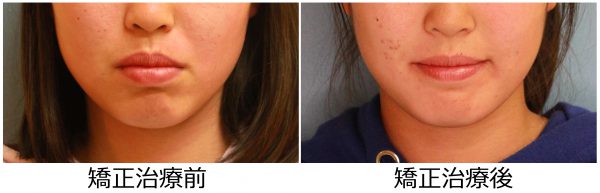

14歳 女性 「 口が 閉じにくい 」 ( 上下顎前突症 )

14歳の 女性です。

”出っ歯” と口もとを治したいとの事で来院されました。

前歯の重なりが気になります。

上の前歯が 傾斜しているため

口もとが 大きく出っ張っています。

お母さんとご本人で来院されたのですが、

お母さんが 娘さんの「もっさりとした」口もとを気にされていました。

このため、お口が 閉じにくいそうです。

また、口元が出っ張っているため 口角が上がらず 不機嫌そうな口もとに見えてしまいます。

叢生を伴う 上下顎前突症 です

口もとの 出っ張り感と 前歯のねじれを治したい

との事で上下左右の抜歯を行い 前歯を後方に移動させ口もとを下げました。

2018年の3月30日にスタートして 2019年の10月15日に 終 了 しました。

治療期間は 19か月でした

前歯の”出っ歯”と重なり は解消され、前歯は 大きく下がりました。

口もと の出っ張り感は 解消されました

口もとの 印象が 大きく変わりました

素敵な笑顔になりました! (#^.^#)

14歳 女性 叢生を伴う 上下顎前突症 治療期間18か月 唇側矯正装置(ホワイトワイヤー)を使用した上下顎第一小臼歯抜歯治療 参考治療費 約65万円 (精密検査から終了まで) 矯正治療に伴う副作用の歯肉退縮、知覚過敏、失活、歯根吸収などは認められませんでした。